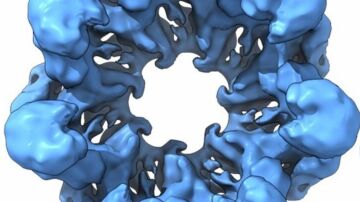

Técnicamente, el equipo en el que trabaja el experto español ha demostrado en ratones que una población de neuronas superficiales de la médula espinal controla un marcador epigenético conocido como pS10H3.

Para el investigador español, “pS10H3 es un novedoso marcador del procesamiento del dolor en neuronas de la médula espinal, y los cambios derivados de él son fundamentales para el normal desarrollo del dolor, lo que abre nuevas posibilidades terapéuticas”.